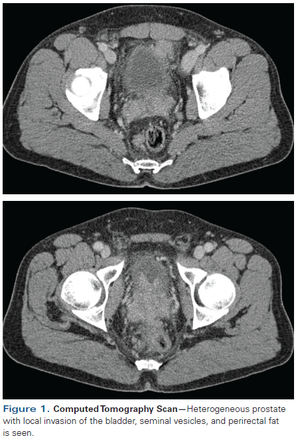

A 55-year-old Hispanic male presents with a family history of gastric cancer in one sibling and prostate cancer in an older brother. CT performed in March 2015 for IMT surveillance showed a heterogeneous prostate with local invasion involving the bladder, seminal vesicles, and perirectal fat.